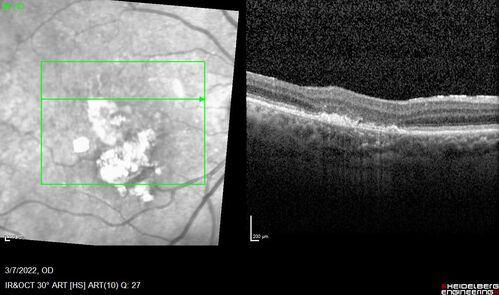

Pigment epithelial detachment with cholesterol crystals

Onion sign

Pigment epithelial detachment with cholesterol crystals - onion sign